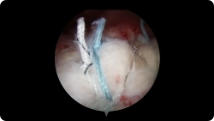

Arthroscopic image of a rotator cuff tear Arthroscopic image of a repaired rotator cuff

Rotator Cuff Tear

Rotator Cuff Repair